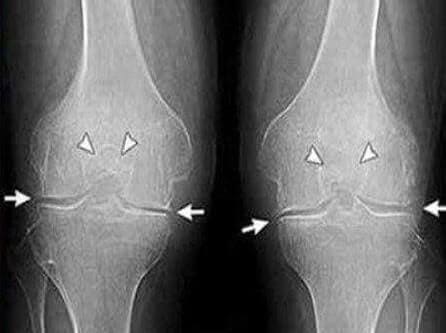

35 diena: išlaikiau testus ir pasidariau rentgeno nuotraukas. Jokių artrozės pėdsakų! Kremzlės sąnariuose kaip 30 metų. Specialistė sakė, kad ankstesnis rentgenas greičiausiai buvo su defektu, todėl artrozės diagnozė buvo klaidinga.